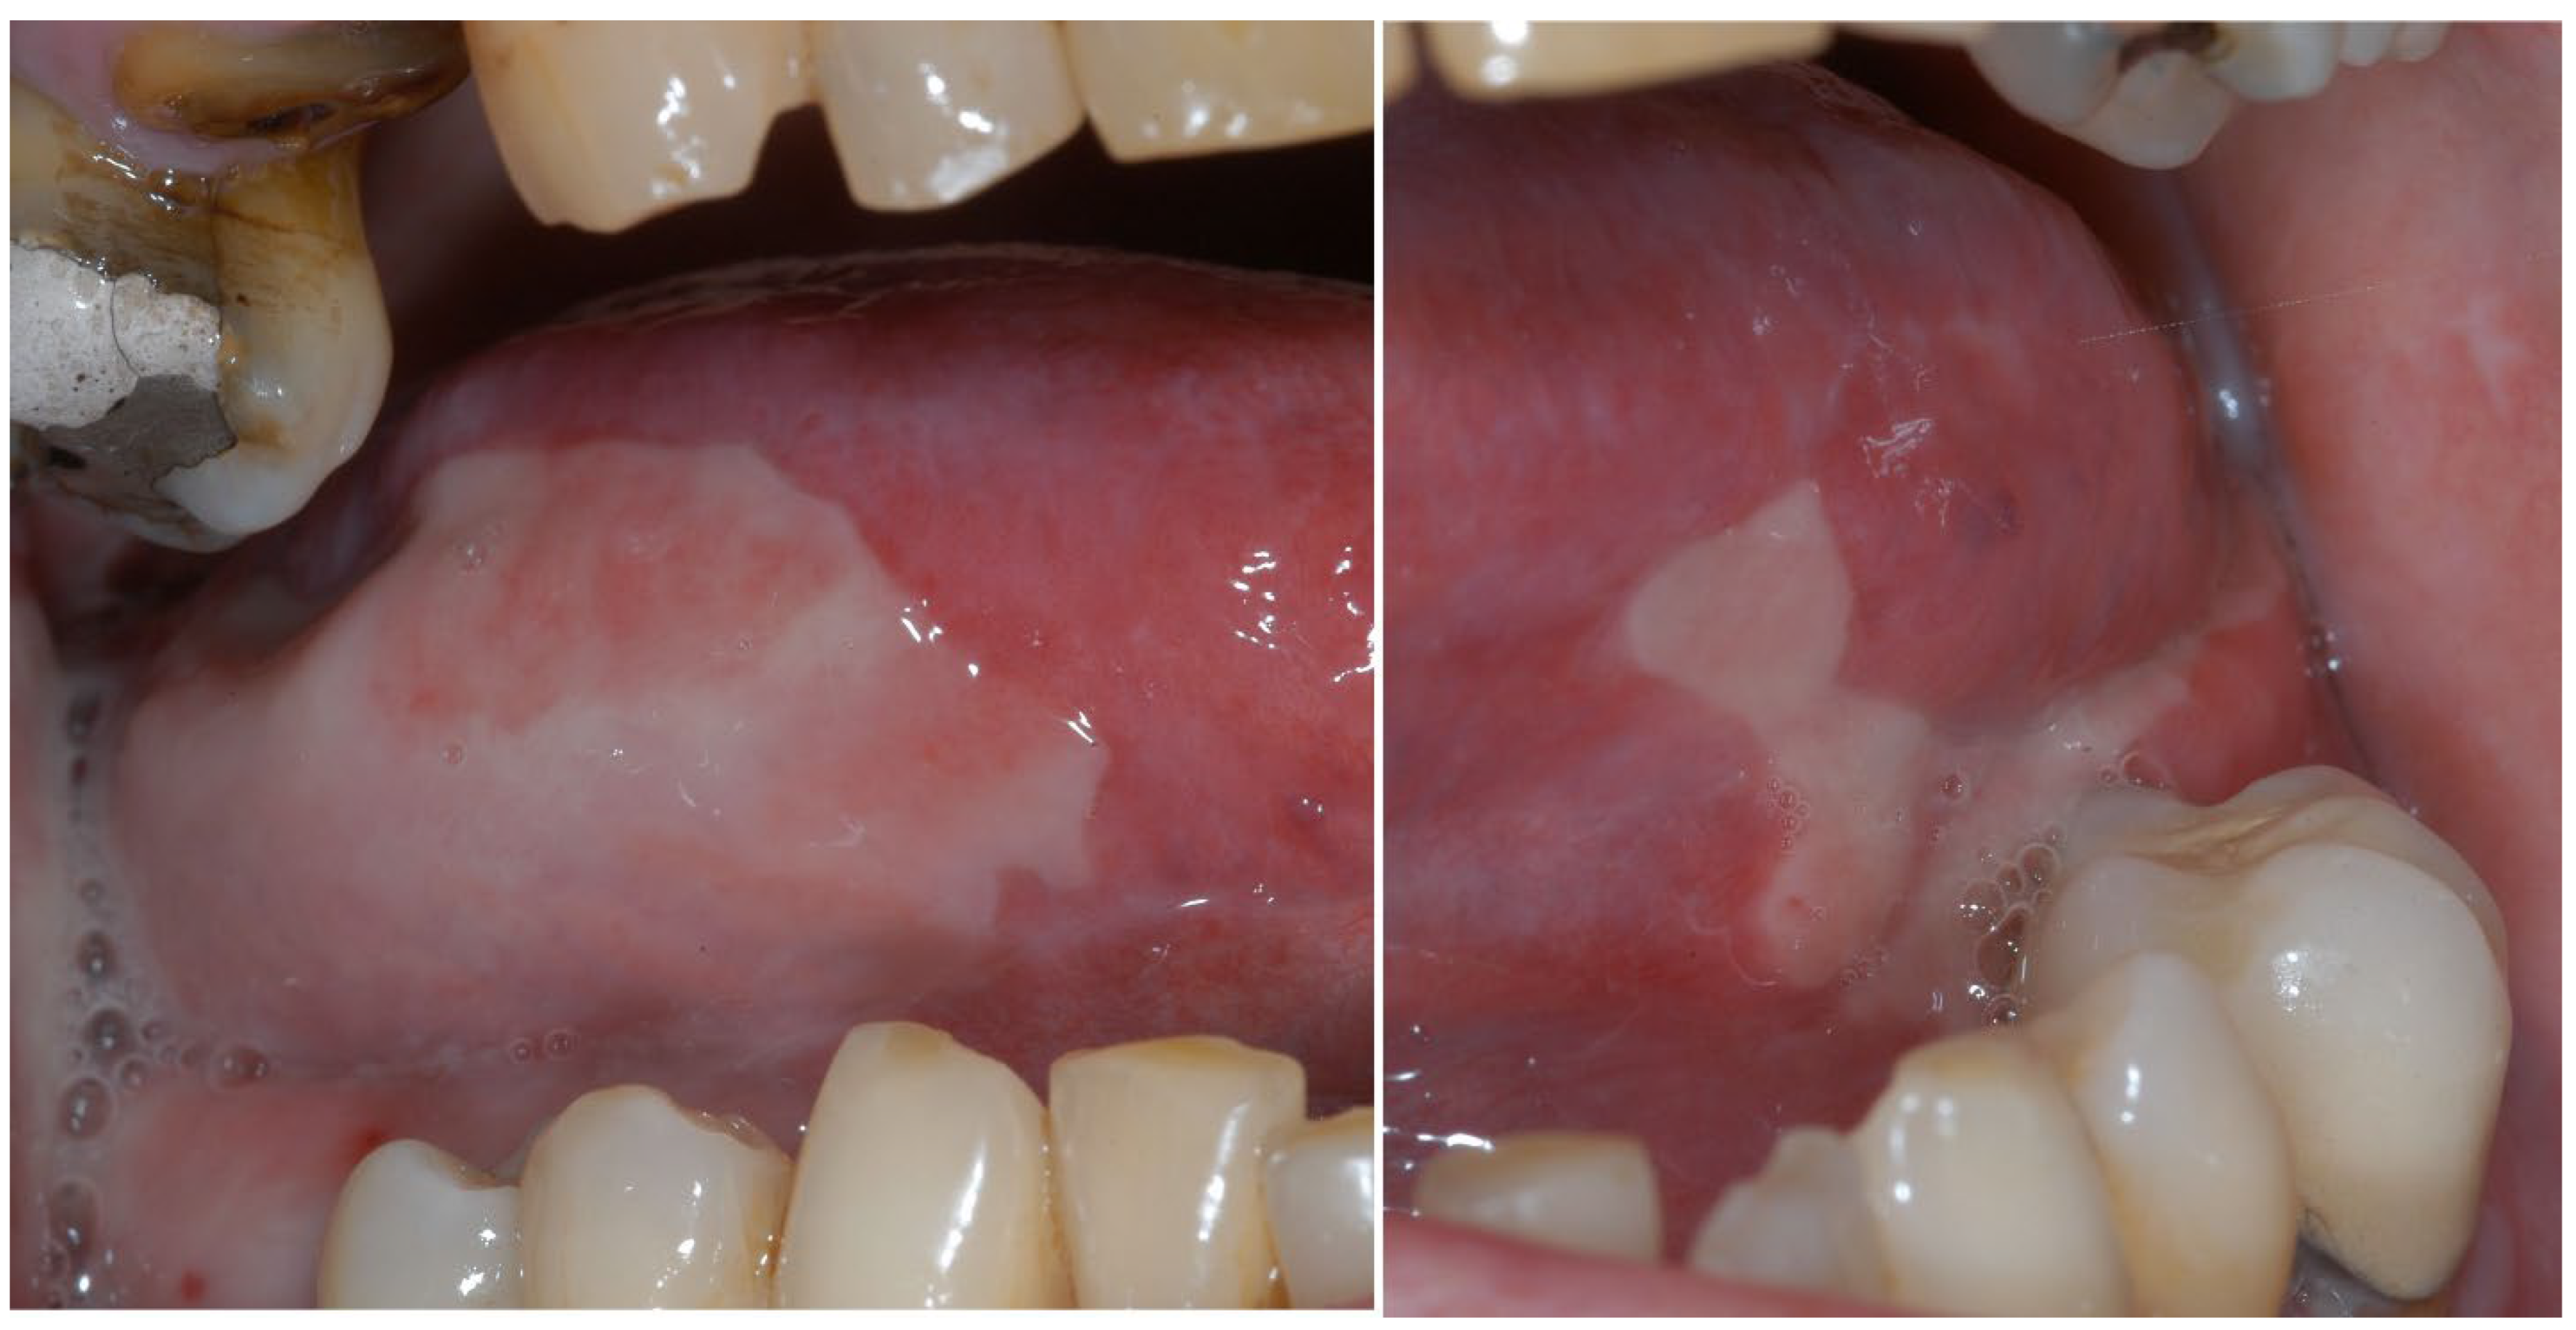

2. Oncology Patients on Antiresorptive/Antiangiogenic Medications

2.1. Prevention and Management of MRONJ